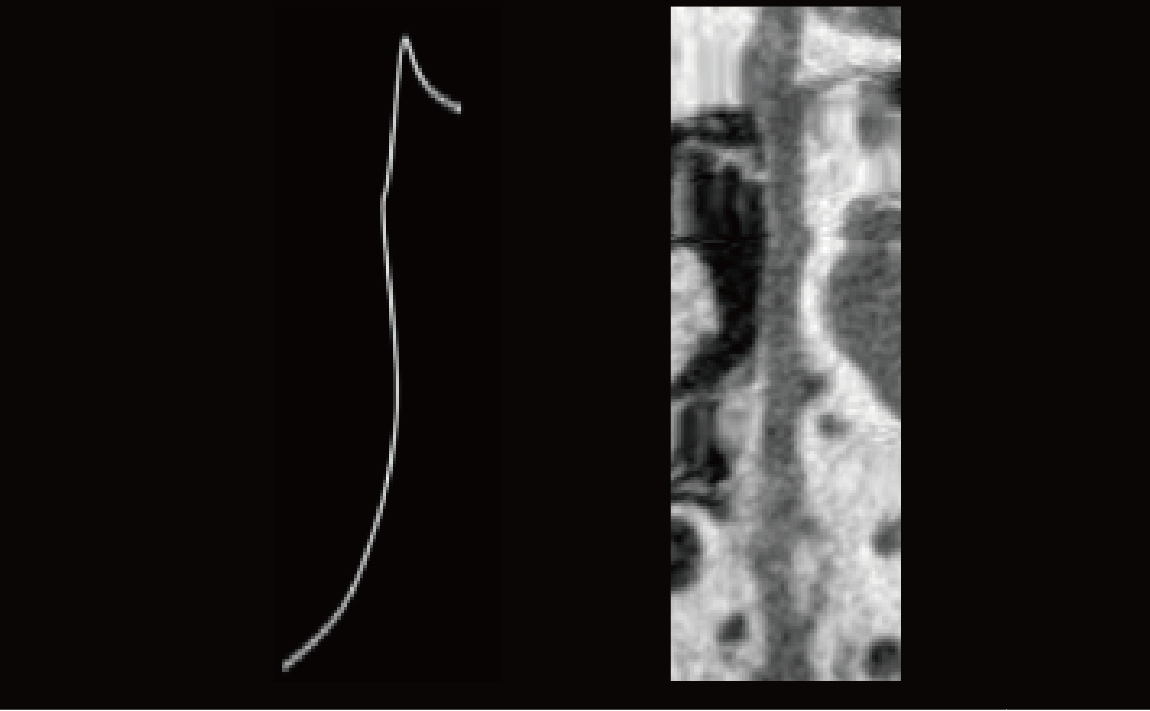

CPR-Surface Reconstruction

Precisely identify the centerline of the tubular structure based on a semi-automatic method. Visualize 3D curved tubular structures with advanced resampling algorithms to 2D image sequences, enabling intuitive inspection of tubular structures.